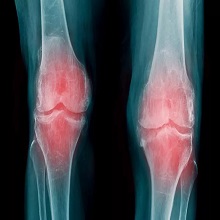

| Једна од веома честих болести колена у општој популацији је остеоартритис. То је хронична болест дегенеративне природе тј. последица је измена у ткивима која сачињавају зглоб, а које настају процесом старења организма. Остеоартритис није специфичан за одређене зглобове, већ може захватити било који. Када је зглоб колена захваћен, то се назива гонартроза. |